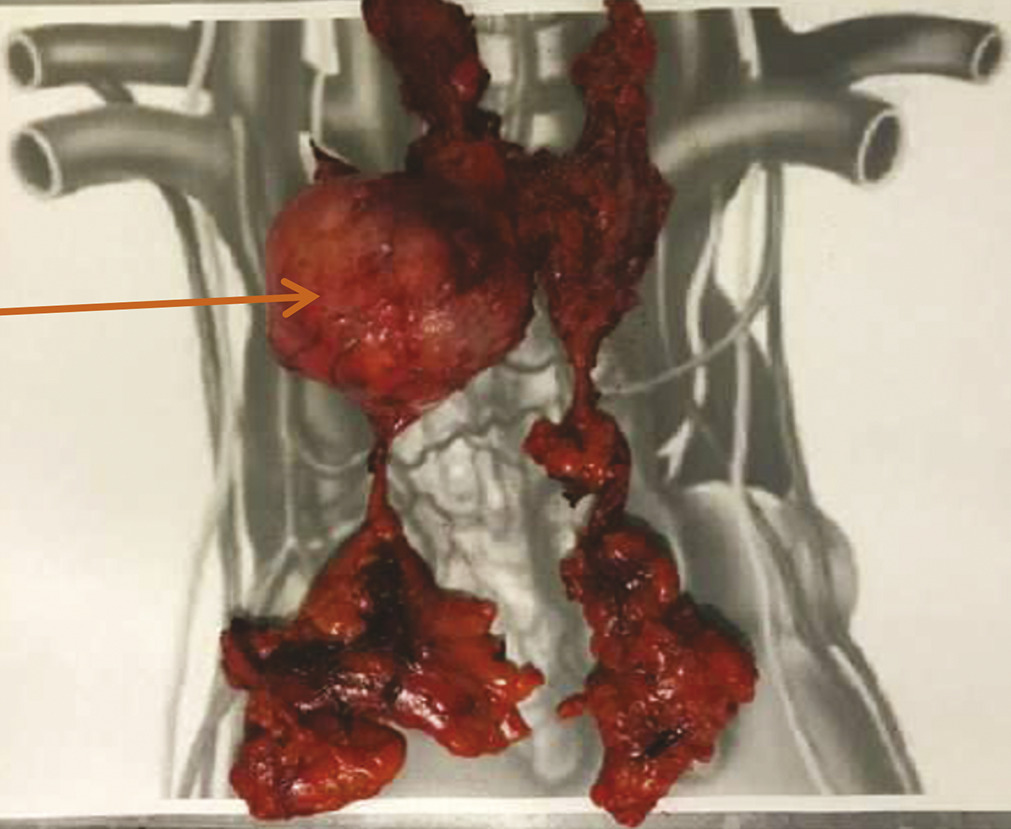

Une évaluation neurologique est nécessaire afin d’encadrer le geste chirurgical. Mme C. reçoit ainsi en préopératoire une injection d’immunoglobulines par voie intraveineuse afin d’éviter une exacerbation des symptômes myasthéniques en périopératoire. La chirurgie consiste en une sternotomie médiane, avec exérèse de la tumeur médiastinale et bilobectomie supérieure. Face à l’envahissement péricardique et pulmonaire adjacent, la tumeur est classée stade III (dans la classification de Masaoka-Koga), et stade T3N0M0, soit IIIA (dans la classification TNM). Les marges de résection sont saines (R0).6, 7

L’exérèse complète monobloc doit être le souci permanent, garantissant à elle seule un bon pronostic.

La thymectomie doit être associée à la thymomectomie.